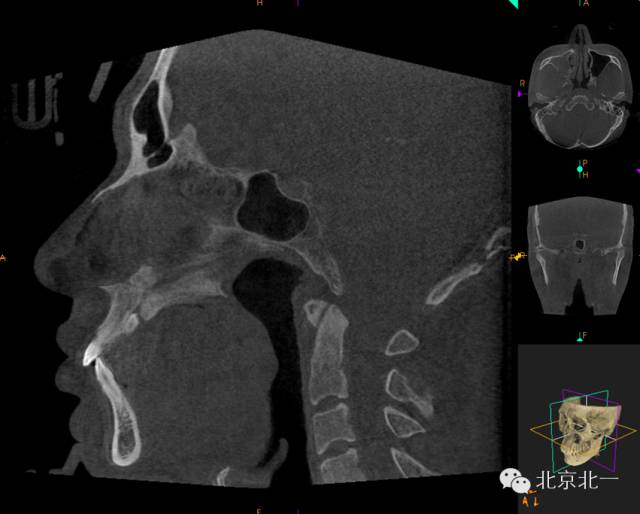

CBCT顯示埋伏多生牙位于腭側(cè)高位,接近切牙管開(kāi)口位置。

CBCT矢狀位顯示多生牙倒置阻生,位于鼻腭神經(jīng)管口